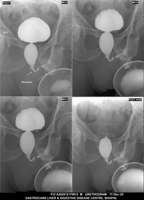

Section: URETHROGRAM

Total: 95 Cases